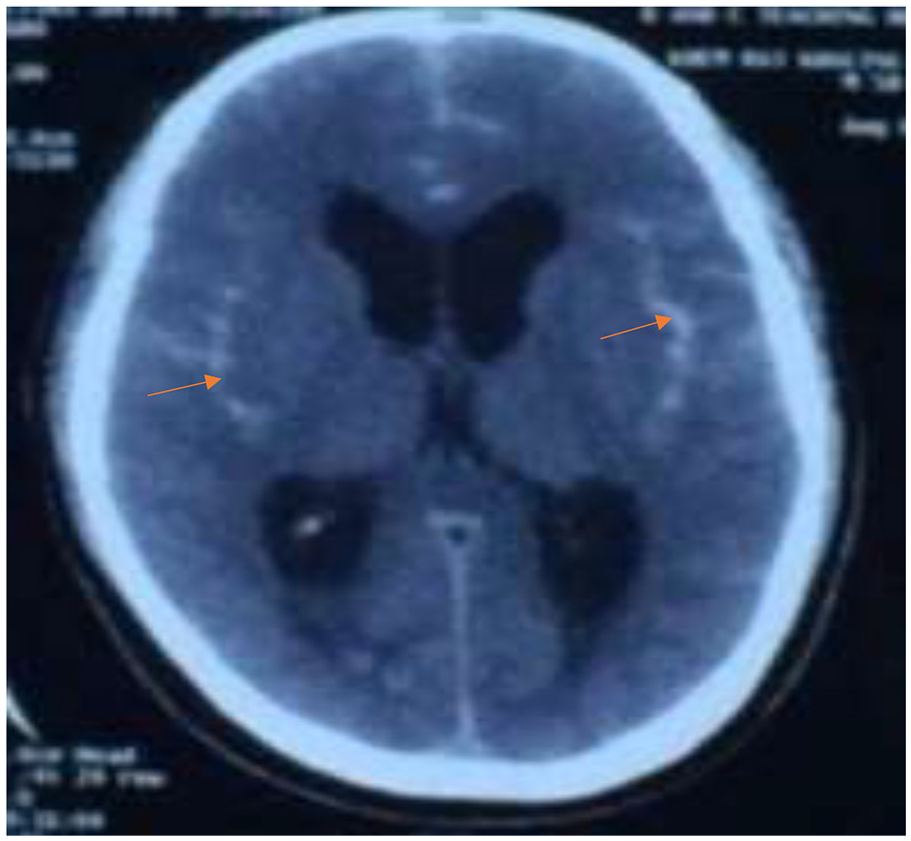

At the time of presentation to the hospital, she had blood pressure, oxygen saturation, heart rate, and temperature of 180/90 mm of Hg, 97% under room air 74 times/min and 98°F, respectively. Upon examination, both pupils were round, regular, and reactive, neck rigidity absent, with plantar reflex upgoing on the right. Other systemic examinations were unremarkable. The electrocardiogram showed normal sinus rhythm. The echocardiogram and bilateral carotid Doppler ultrasound were unremarkable. A non-contrast computed tomography (NCCT) scan of the head showed hyper-densities involving the bilateral cerebral cortical sulcus, and Sylvian fissure suggesting a subarachnoid hemorrhage (as in Figure 1). The patient underwent a computed tomography angiogram (CTA) which demonstrated a complex ACOm aneurysm (as in Figure 2). Further 3D construction arteriogram sequence demonstrating large lobulated saccular aneurysm noted at the ACOm (as in Figure 3).

Axial computed tomography scan shows hyper-densities involving the bilateral cerebral cortical sulcus, and Sylvian fissure suggesting subarachnoid hemorrhage.